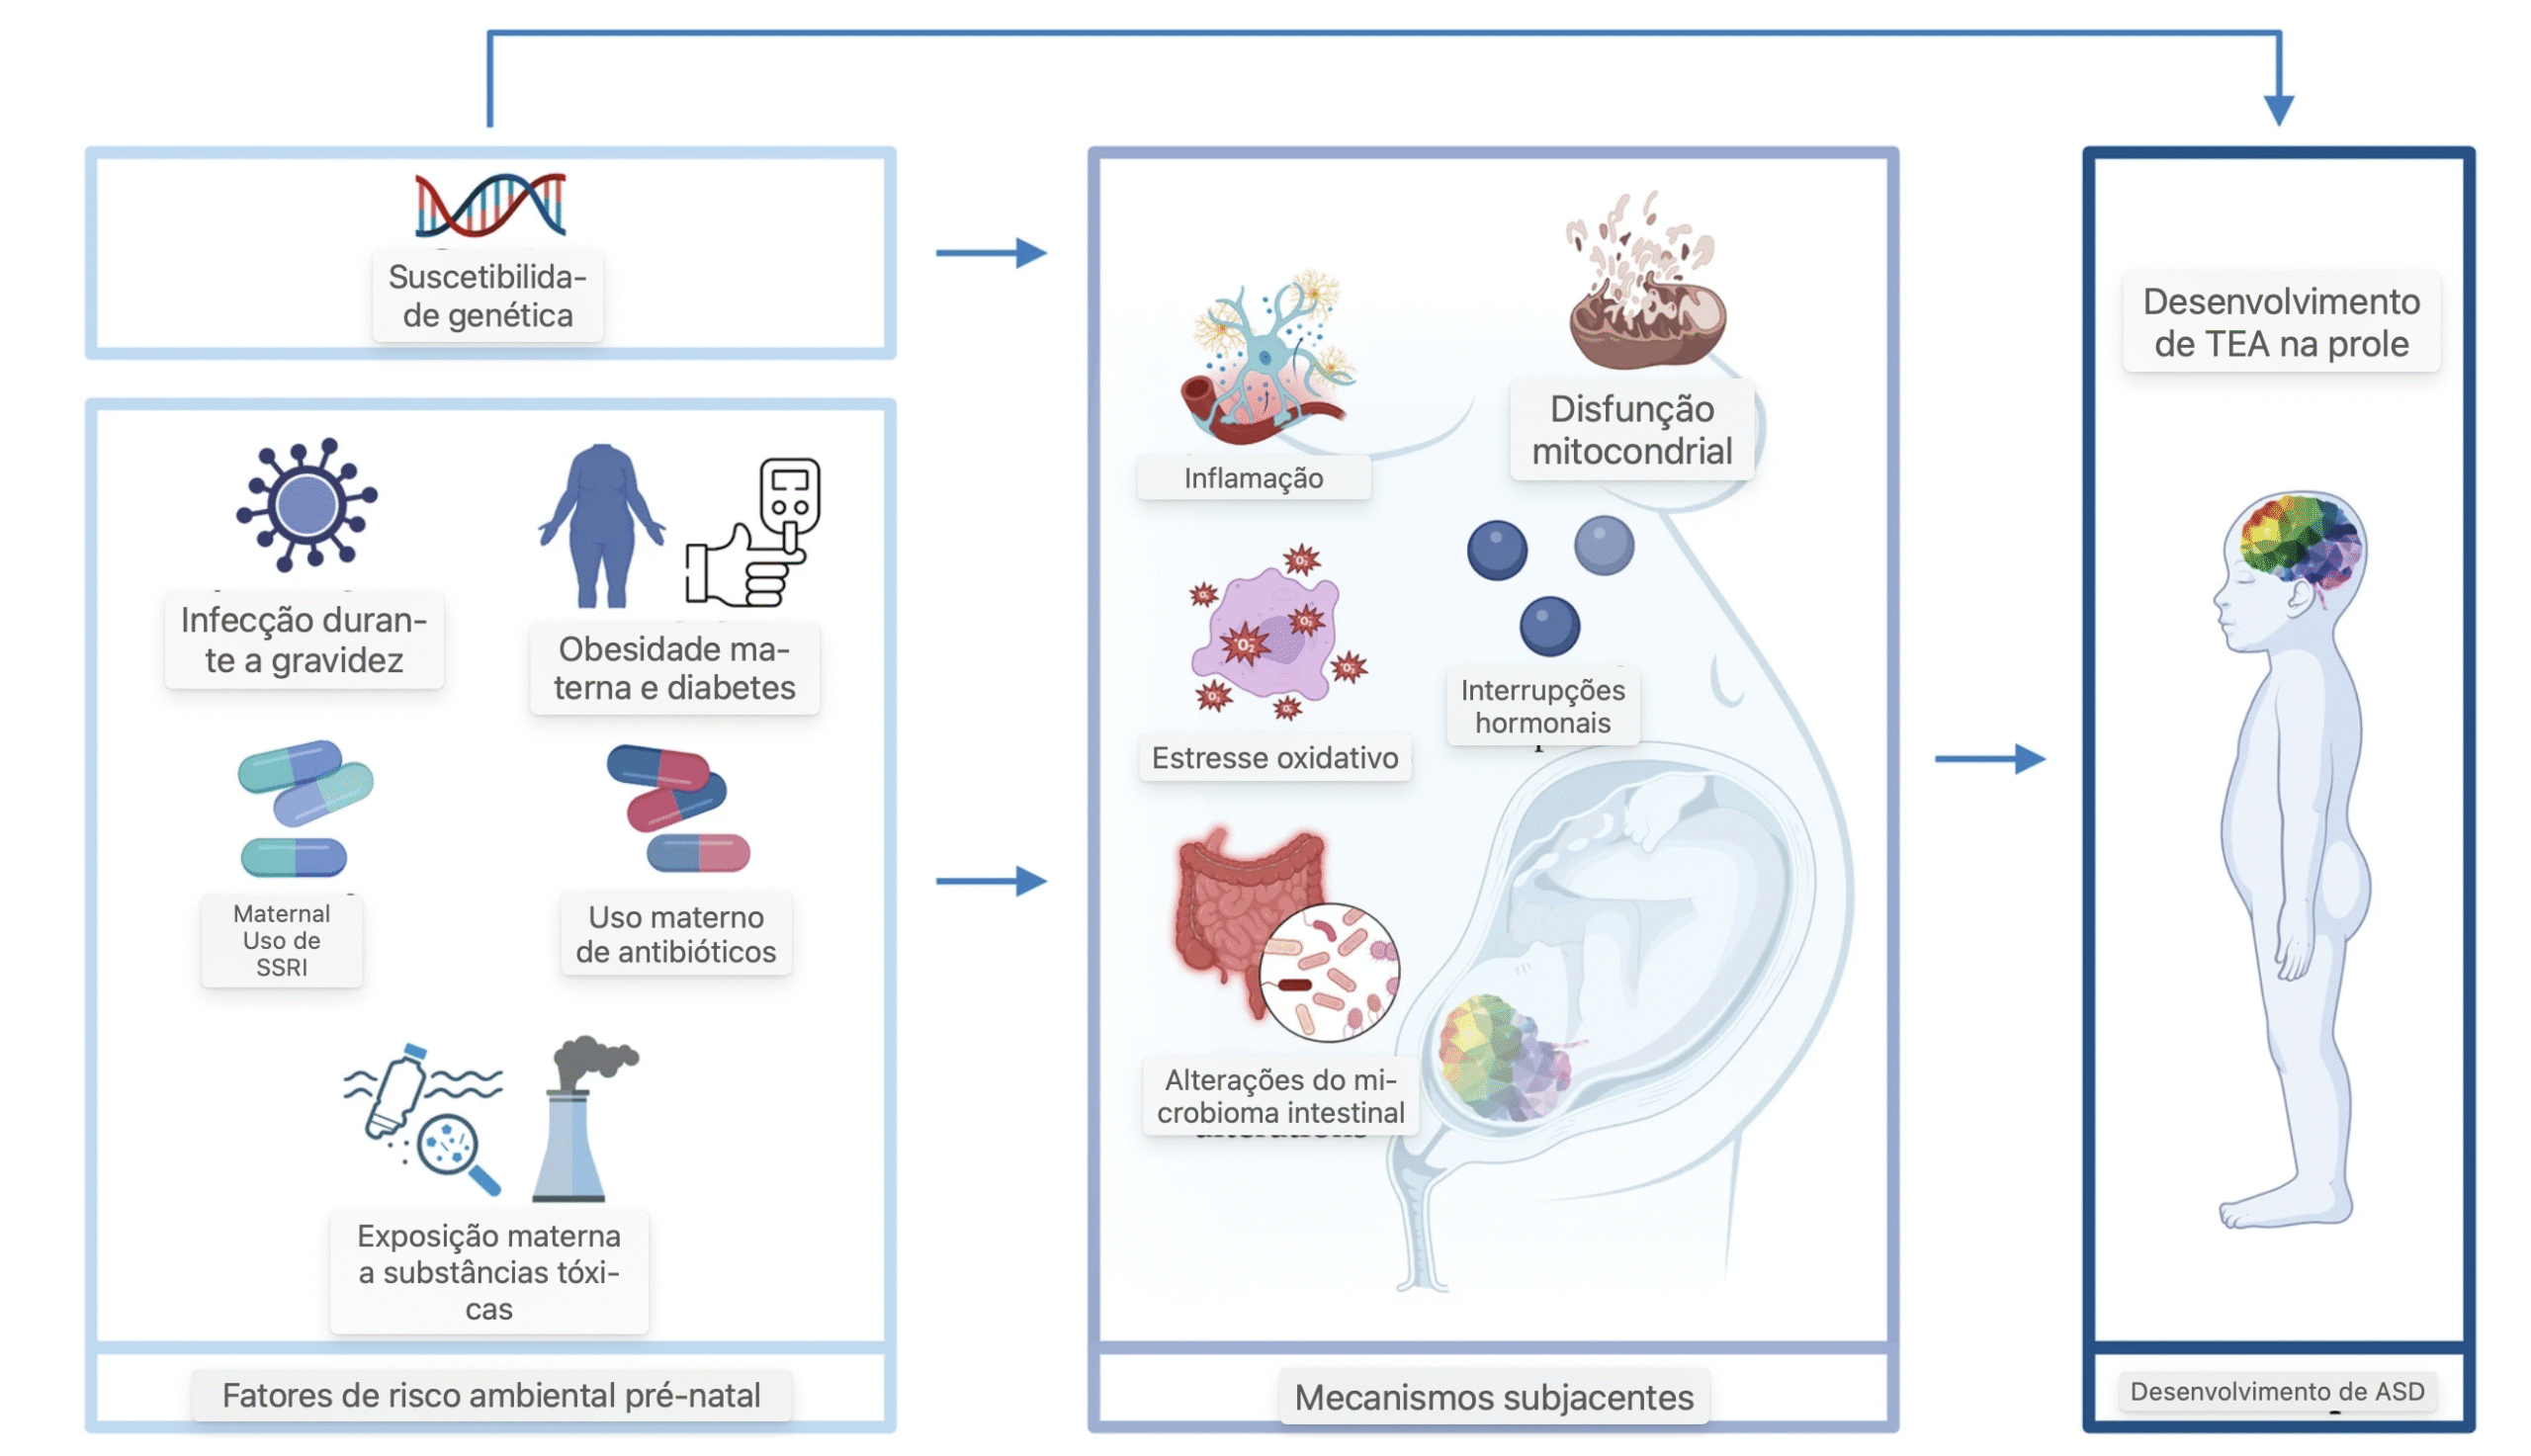

A etiologia do TEA é multifatorial, envolvendo uma combinação de predisposição genética e exposições ambientais. Fatores pré-natais associados ao ambiente materno, como infecções, doenças metabólicas e medicamentos, podem impactar vias críticas do desenvolvimento fetal, especialmente em indivíduos geneticamente suscetíveis. Esses fatores afetam processos como a neurogênese, o metabolismo mitocondrial e o microbioma intestinal.

Um diagrama esquemático resumindo os fatores de risco ambientais pré-natais para o transtorno do espectro do autismo (TEA) e seus mecanismos potenciais. Da esquerda para a direita, o painel esquerdo descreve a suscetibilidade genética e os fatores de risco ambiental pré-natais, como infecção durante a gravidez, obesidade materna, diabetes, inibidor seletivo da recaptação da serotonina (ISRS) e uso de antibióticos e exposição a substâncias tóxicas. O painel central detalha os mecanismos subjacentes para esses fatores de risco, incluindo inflamação, disfunção mitocondrial, interrupção hormonal, estresse oxidativo e alterações no microbioma intestinal que estão associadas ao desenvolvimento de TEA na prole retratado no painel à direita

Infecções Maternas: Um Risco Ampliado

Infecções virais ou bacterianas durante a gravidez, como rubéola e citomegalovírus, podem aumentar o risco de TEA em até 2,8 vezes, principalmente no primeiro trimestre. A ativação imune materna (MIA) gera respostas inflamatórias que podem atravessar a placenta, interferindo na formação neurológica fetal, por mecanismos como estresse oxidativo e disfunção mitocondrial.

Obesidade e Diabetes Gestacional

Obesidade e DMG aumentam o risco de TEA entre 1,3 e 2 vezes, especialmente quando o diagnóstico é anterior à 26ª semana de gestação. Essas condições estão associadas a inflamação crônica, alterações hormonais e disbiose intestinal, afetando diretamente o desenvolvimento fetal. A combinação entre obesidade e DMG potencializa esses efeitos.

Uso de Medicamentos: ISRS e Antibióticos

O uso de ISRS durante a gestação, especialmente no primeiro trimestre, pode aumentar de 1,5 a 4,5 vezes o risco de TEA. Embora haja viés de indicação, estudos mostram que esses medicamentos alteram os níveis de serotonina e afetam a formação do sistema nervoso fetal.

O uso de antibióticos também está relacionado a risco aumentado de TEA, por sua influência na microbiota intestinal da mãe, que pode afetar a saúde placentária e o sistema imunológico fetal.

Exposição a Poluentes e Metais Pesados

A exposição a ftalatos, poluição do ar e metais como chumbo, mercúrio e cádmio está ligada a estresse oxidativo e alterações epigenéticas. Esses agentes tóxicos podem afetar a expressão de genes envolvidos no desenvolvimento neurológico, especialmente em meninos, sugerindo interação com hormônios sexuais.

Mecanismos Subjacentes

- Desregulação imunológica: inflamação crônica altera circuitos neurais.

- Disfunção mitocondrial: afeta produção de energia essencial.

- Estresse oxidativo: danifica estruturas neurais.

- Alteracões no microbioma: influenciam a placenta e a imunidade.

- Mudanças epigenéticas: modificam a expressão de genes-chave.

Esses mecanismos muitas vezes atuam em sinergia, amplificando o risco em indivíduos com predisposição genética.